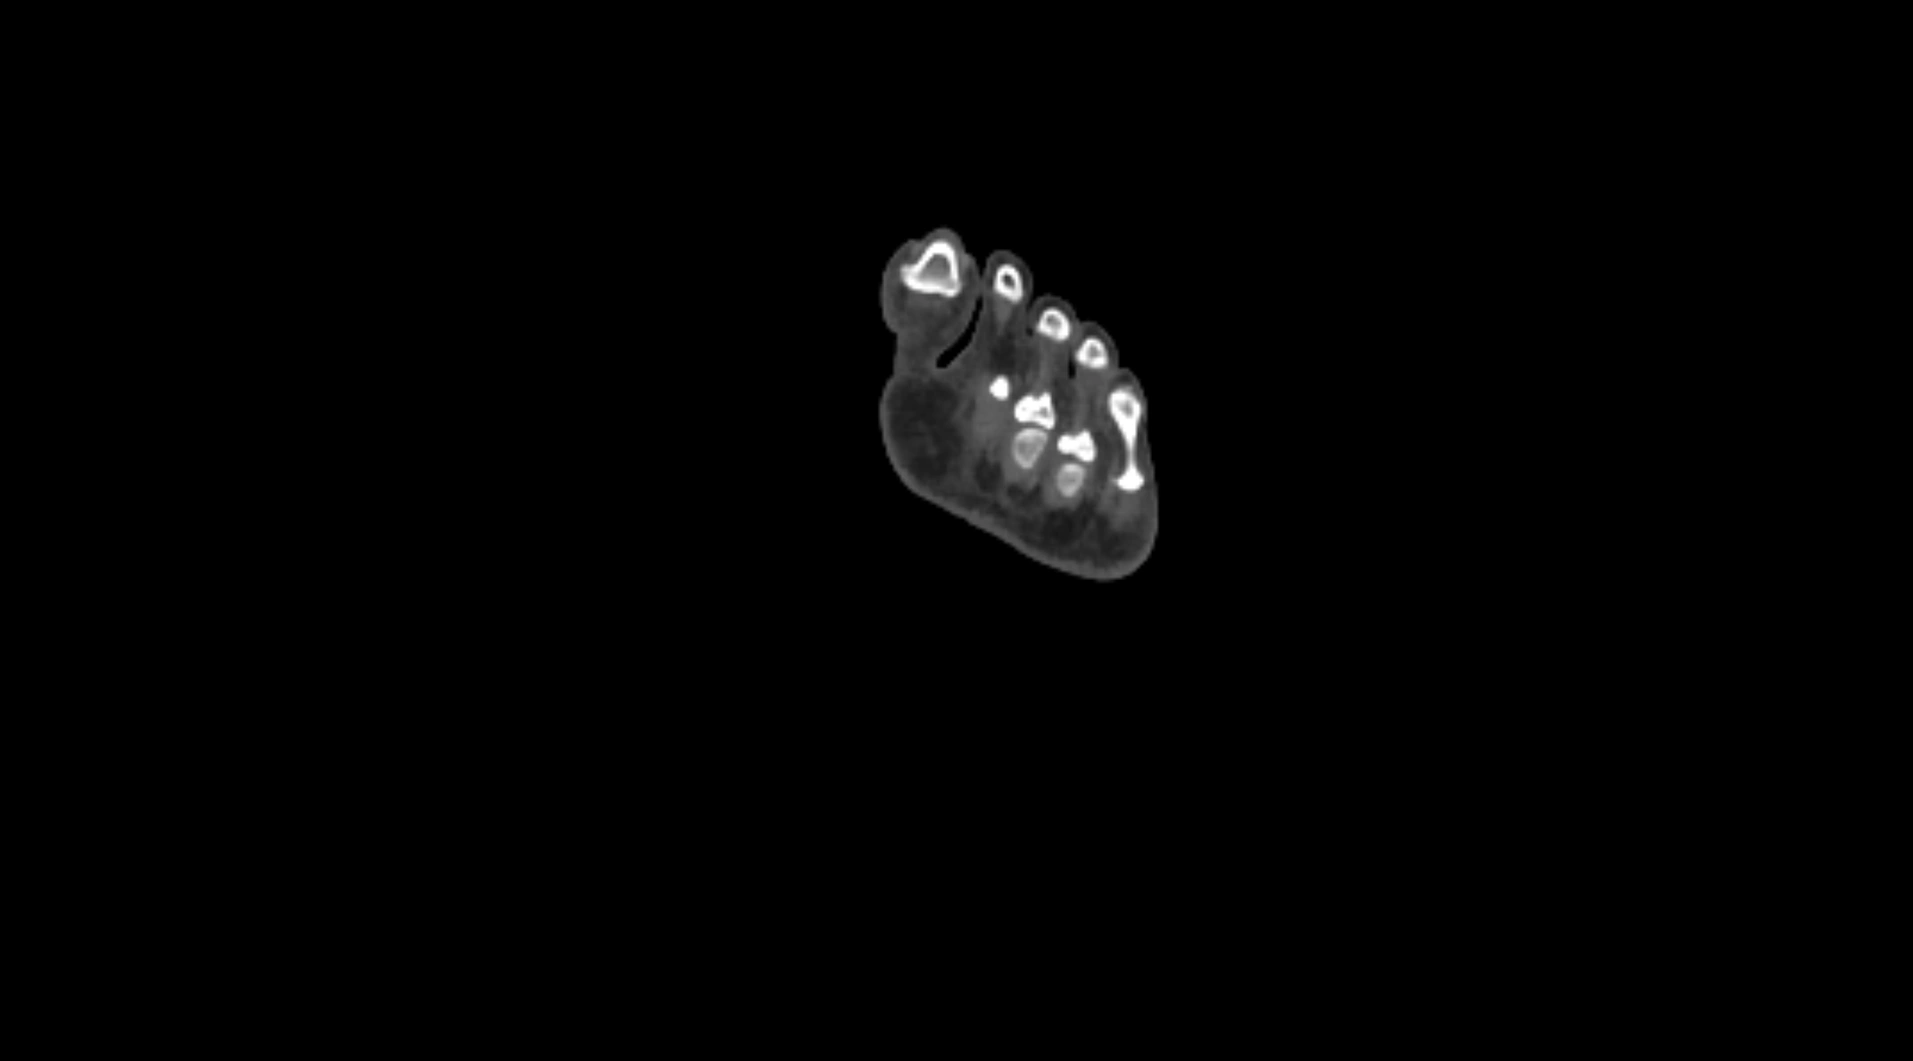

CT images

image